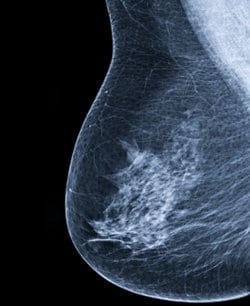

נשים החולות בסרטן השד עומדות בפני סיכון מוגבר לתחלואה קרדיווסקולארית עקב ההשפעות הרעילות של חלק מהטיפולים במחלה. כך על פי הצהרה מדעית שפרסם ב- American Heart Association. נתונים נוספים העשויים להיות בעלי משקל הינם הימצאות גורמי סיכון חופפים הן לסרטן השד והן ל- CVD, כולל עישון, השמנה ודיאטה מערבית.

ההצהרה שפורסמה בכתב העת Circulation מפרטת את הטיפולים לסרטן השד העשויים להגביר את הסיכון ל- CVD, לדוגמא – anthracyclines וטיפול מוכוונים HER-2 קשורים עם פגיעה בפעילות החדר השמאלי ואי ספיקת לב, בעוד שהקרנות מגבירות את הסיכון ל- coronary artery disease ו- cardiomyopathy. ההצהרה מייעצת בנוגע לניטור היארעות מוקדמת של רעילות ללב ובמידת הצורך שיקולים לבחירת טיפול חליפי.